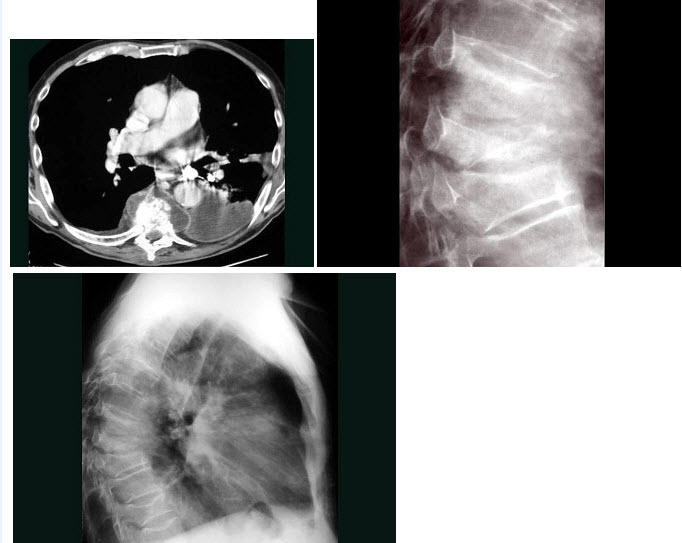

253、单项选择题

男,71岁,背部酸痛,低热,乏力,消瘦2月余,结合影像学表现,最可能的诊断是()

A.脊柱转移瘤

B.化脓性脊柱炎

C.脊椎结核

D.椎体压缩骨折

E.阻滞椎